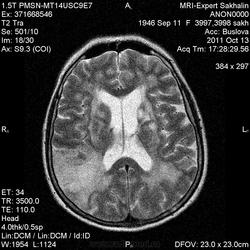

Ишемический инфаркт

Вот, Сергей Николаевич, я тоже указала, что НМК по ишемическому справа в СМА

ОНМК по ишемическому типу в бассейне правой СМА. Судя по очагам накопления в коре, подострое.

Последствия ОНМК с геморрагическим пропитыванием справа. Кистозно-атрофические изменения в левой гемисфере мозжечка (последствия ОНМК ). Множественные очаги сливного характера вещества головного мозга ( поля лейкоариоза)

Писал писал и куда-то все пропало, в общем, это не последствия инфаркта в бассейне сма.

Да хотела еще добавить возможно у пациента еще были лакунарные инсульты. В области базальных ядер( слева ) определяются кисты, окруженные глиозом. И на предпоследнем изображение в правой гемисфере мозжечка по- моему и также есть нмк.

Гглиоз, сосудистые очаги, лейкоареоз - это все при ДЭП, этим и обусловлена деменция.